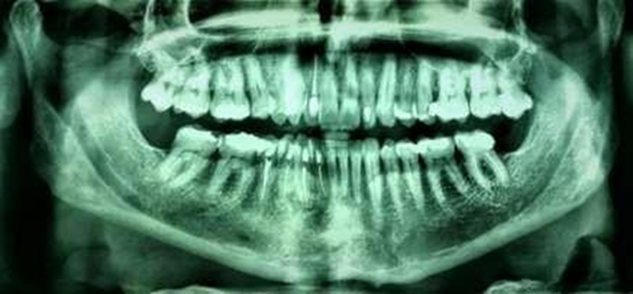

Figure 2. Initial panoramic

radiograph showing multilocular bone appearance

1). Radiographic and tomographic examination (Figure 2 & Figure 3)

revealed an ill-defined multilocular radiolucency, with “honeycomb” aspect,

adjacent to the roots of the lower right canine and premolars, without

mandibular base involvement. Pulp vitality test was applied using endofrost

(cold) and gutta percha (heat), revealing vital canine and non-vital premolars.

The differential diagnosis was Ameloblastoma, botryoid cyst and central lesion

of giant cells.